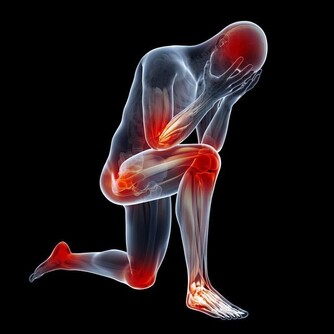

又有一位女士,因雙手發麻來診。按經絡上講,手指的哪一指發麻,應與相對應臟腑的功能失調有關,但兩隻手的手指全麻,病因就不一樣了,應該與頸椎椎體的錯位有關。於是,我按照整脊復位法,檢查她頸椎排列的形態。檢查頸椎排列時,發現頸椎第六椎椎體向右側凸起,凸出的這一椎體無疑是手指發麻的病因。根據發麻的病因,採用整脊復位的方法,將錯位的椎體復位,僅幾天的複位治療,錯位的椎體就復位了,結果發麻的手指變化不大。錯位的椎體已經歸位了,病症為什麼沒有大的好轉呢?

這說明對病因的判斷有誤。接著再次檢查病因,順著頸椎向下檢查胸椎時,發現胸椎的第一椎體向右凸出,胸椎第二椎體向左凸出,其他胸椎排列正常,在檢查胸椎中發現了新的情況。根據檢查出來的病因,採用整脊復位方法,對胸椎錯位的椎體進行複位,僅經過五天的複位治療,胸椎錯位的椎體復位了,兩手手指也不再發麻了。

通過臨床看到,頸、腰椎錯位,只是頭痛或者是手麻病症其中的一個病因,但絕不能忽略頸、腰椎之外的病因。從十二經筋在人體的分佈上看,胸一椎至十椎的周圍佈滿了肌組織,其中斜方肌是肌組織當中一塊較大的肌肉,它分佈在頸椎的兩側,胸椎上部的兩側以及肩部(腰部亦與此相同),這些肌肉、肌組織也要依靠氣血的供養,維持肌肉、肌組織的運動功能。

胸椎的每個椎體,均與臟腑相通,是通往臟腑並為臟腑提供氣血的通路,當胸椎第一、二椎體發生了錯位,必然造成通往頸椎,肩膀的經脈運行受阻,氣血循環不暢,影響對頸椎和胳膊等部位的供血,導致通往頭部和肩部經絡受阻,血液循環不暢通,因而在頭部出現疼痛和胳膊發麻的病症。當錯位的胸椎經復位治療,一旦復位“開閘放水”,經脈通暢,活血化瘀,就迅速的滿足了頭部和胳膊缺血的需要,使頭痛和手指發麻的病症及時得到恢復。